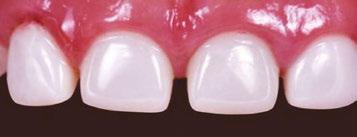

Several clinical solutions exist for primary anterior teeth with multisurface decay. Full coronal restoration of carious primary incisors may be indicated when caries is present on multiple surfaces, pulpal therapy is indicated, caries may be minor, but oral hygiene is very poor, or in a child with severe early childhood caries or a high caries risk diagnosis.1 Depending on the clinical scenario, a minimally invasive approach with the utilization of a high viscosity glass ionomer cement (HVGIC), with or without the combination of silver diamine fluoride (SDF) in a strip crown form, may pause the caries progression and provide an adequate clinical solution. Resin composite strip crowns have shown 80% retention rates and adequate parental satisfaction,1-4 although composite resin strip crowns have shown lower retention rates in teeth with decay involving three or more surfaces and particularly in children with a high caries risk4-6 (Figure 1). This could be from the continued high caries risk behaviors of the patient, as composite resin strip crowns in this population have shown to have increased inflamed marginal gingiva and gingival bleeding, increased plaque retention along the restoration, and loss of some restorative material.5,6

2: NuSmile® Anterior Zirconia crowns at 2-year follow up. Note the high amount of plaque accumulations along the untreated cuspid and existing stainless-steel crowns

Figure 1: Occlusal films at recall visit in high caries risk patients showing loss of material and recurrent decay in composite resin strip crowns Figure